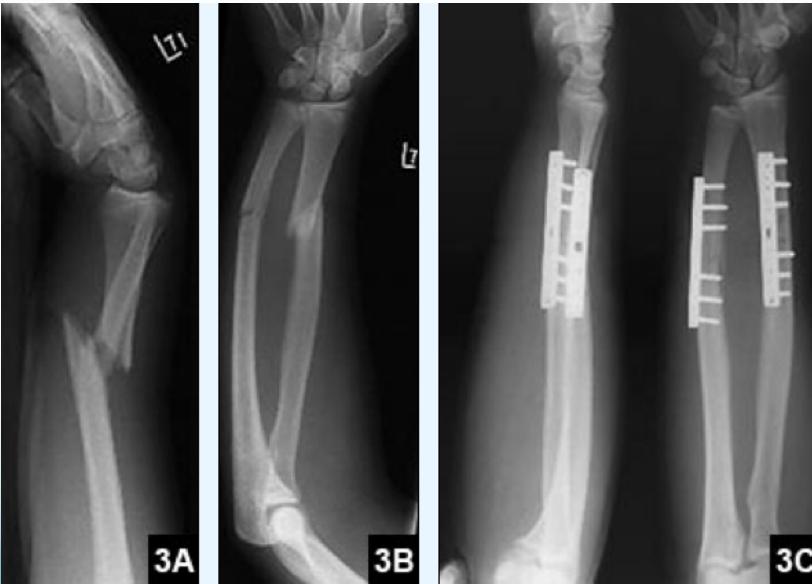

Plating

Monteggia

A Monteggia fracture is defined as a proximal 1/3 ulna fracture with an associated radial head dislocation.

Galeazzi

A Galeazzi fracture is a distal 1/3 radial shaft fracture with an associated distal radioulnar joint (DRUJ) injury.